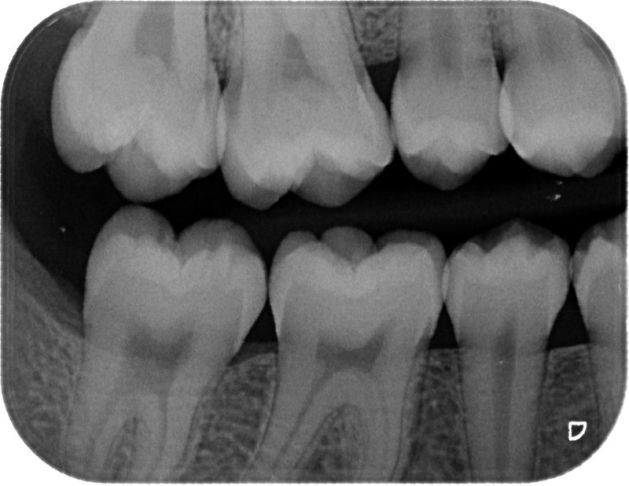

E’ particolarmente indicata per visualizzare in modo specifico l’anatomia di un determinato elemento dentale (corona, radice del dente, tessuto gengivale) quando si sospetti una patologia circoscritta ad un singolo elemento.

Grazie al digitale si ottiene un’immagine più grande e definita che permette di migliorare la diagnosi.